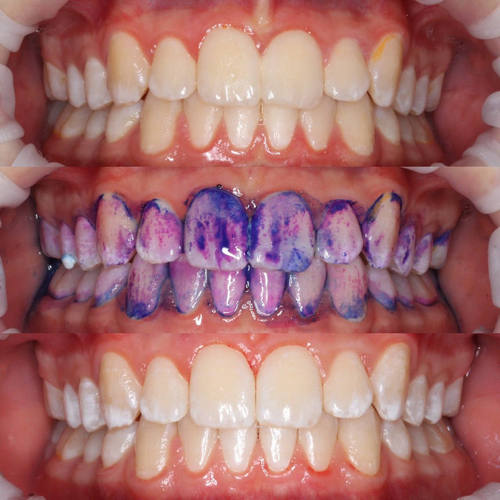

Уровень личной гигиены, кстати, вполне реально оценить объективно. Для этого есть один хороший показатель — гигиенический индекс.

Вычислить его нам поможет специальный индикатор, позволяющий определить не только объём налёта, но и его возраст.

Выглядит немного пугающе, но замечательно счищается вместе с налётом. Зато врач может вполне аргументированно сказать: «Вася, обрати внимание, какой процент поверхности твоих зубов покрыт налётом». В воспитательных целях пациента можно отпустить без чистки). С подростками забавно работает.

Так вот. Мы, конечно, не ждём и не требуем, чтобы все наши пациенты целыми днями занимались только чисткой зубов, забыв про еду и сон, но принимаем в программу только людей, чей гигиенический индекс не ниже 1 (удовлетворительно). Добиться такого вполне реально, если правильно чистить зубы два раза в день: после завтрака и после ужина. О том, как правильно это делать, очень подробно рассказывала моя коллега.

Сразу после окрашивания зубного налёта врач сфотографирует эти фиолетовые зубы и покажет пациенту, где у него самые уязвимые участки. А потом ещё и щётку подарит, и почистить зубы в своём присутствии попросит, и процесс проконтролирует, и советов надаёт.